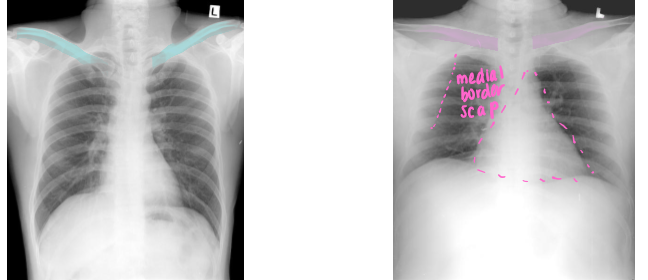

Differentiate which is PA vs AP view. Why

Left PA:

clavicles ELEVATED

medial border of scap NOT in center of lung fields

heart NOT magnified and enlarged

Right: AP

clavicles HORIZONTAL

scapulae in lung fields

heart appears magnified/elarged

labeled PA view